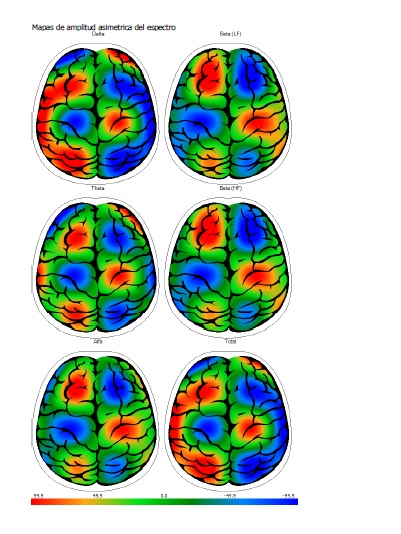

APLICANDO ELECTRO ENCEFALOGRAMA CUANTITATIVO 3D PARA MAPEO CEREBRAL